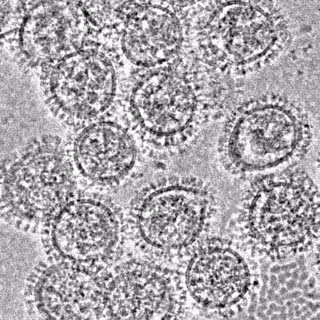

Microscopía crioelectrónica de virus de gripe A

KOSIK ET AL., 2019